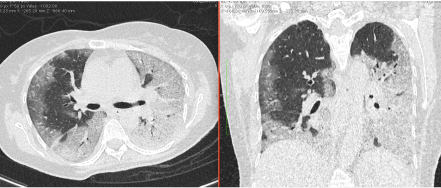

- Изменения в легких при КТ (рентгенографии), типичные для вирусного поражения (объем поражения значительный или субтотальный; КТ 3 - 4)

- Изменения в легких при КТ (рентгенографии), типичные для вирусного поражения критической степени (объем поражения значительный или субтотальный; КТ 4) или картина ОРДС.

Методы лучевой диагностики применяют для выявления COVID-19 пневмоний, их осложнений, дифференциальной диагностики с другими заболеваниями легких, а также для определения степени выраженности и динамики изменений, оценки эффективности проводимой терапии.

КТ имеет высокую чувствительность в выявлении изменений в легких, характерных для COVID-19. Применение КТ целесообразно для первичной оценки состояния ОГК у пациентов с тяжелыми прогрессирующими формами заболевания, а также для дифференциальной диагностики выявленных изменений и оценки динамики процесса. КТ позволяет выявить характерные изменения в легких у пациентов с COVID-19 еще до появления положительных лабораторных тестов на инфекцию с помощью МАНК. В то же время, КТ выявляет изменения легких у значительного числа пациентов с бессимптомной и легкой формами заболевания, которым не требуется госпитализация. Результаты КТ в этих случаях не влияют на тактику лечения и прогноз заболевания при наличии лабораторного подтверждения COVID-19. Поэтому массовое применение КТ для скрининга асимптомных и легких форм болезни не рекомендуется.

5. Рекомендовано проведение лучевого исследования пациентам при среднетяжелом, тяжелом и крайне тяжелом течении ОРИ с целью медицинской сортировки, оценки характера изменений в грудной полости и определения прогноза заболевания:

- выполнение КТ легких без внутривенного контрастирования в стационарных условиях или в амбулаторных - при показаниях к госпитализации;